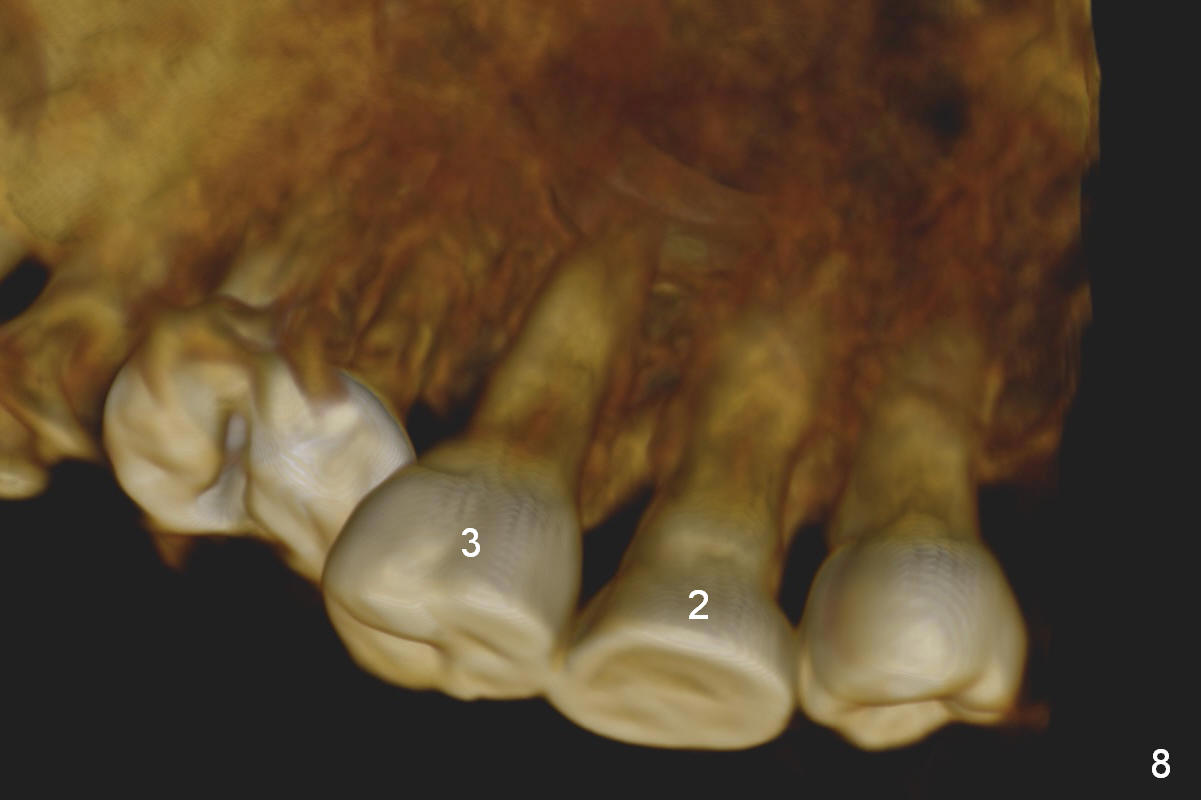

Orthodontic intrusion with mini-implants does not seem to work. When segmental brackets and bands are supplemented, the neighboring tooth (#14) becomes loose. CBCT 3 D and sagittal section show ~3 mm supraeruption of the teeth #2 and 3 (Fig.1,2). Diagnostic wax up demonstrates that the teeth #2 and 3 need to be intruded for 4 and 2 mm, respectively. Buccal gingival sulcus and anterior oblique incisions are shown in Fig.3 (red line). Osteotomy will be made with surgical fissure bur and chisels (Fig.4 red lines). The segment is down fractured (Fig.5 arrow). Apical bone is removed with acrylic bur and/surgical burs (Fig.6 cross lines). The segment is elevated and checked with a prefabricated splint out of diagnostic wax up. Insert a thicker orthodontic wire into brackets and bands buccally.

Fig.8 is a preop palatal view of the region. When the segment is lift (Fig.89 arrow), use a twisted wire (lingual retainer; blue line) and composite (red dots) for fixation. The splint may be also used for fixation. On the right, use a thin ortho wire to tighten the splint against mini implants, while on the left, thin ortho wire and composite will be used. The patient will eat soft diet for several months. Keep good oral hygiene.